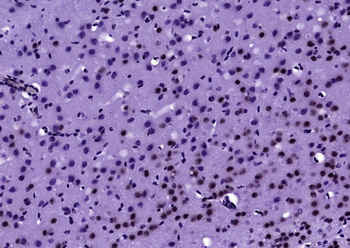

IHC staining of FFPE human brain with Ubiquitin antibody (clone PBQN-1). Required HIER: boil tissue sections in pH9 10mM Tris with 1mM EDTA for 10-20 min followed by cooling at RT for 20 min.